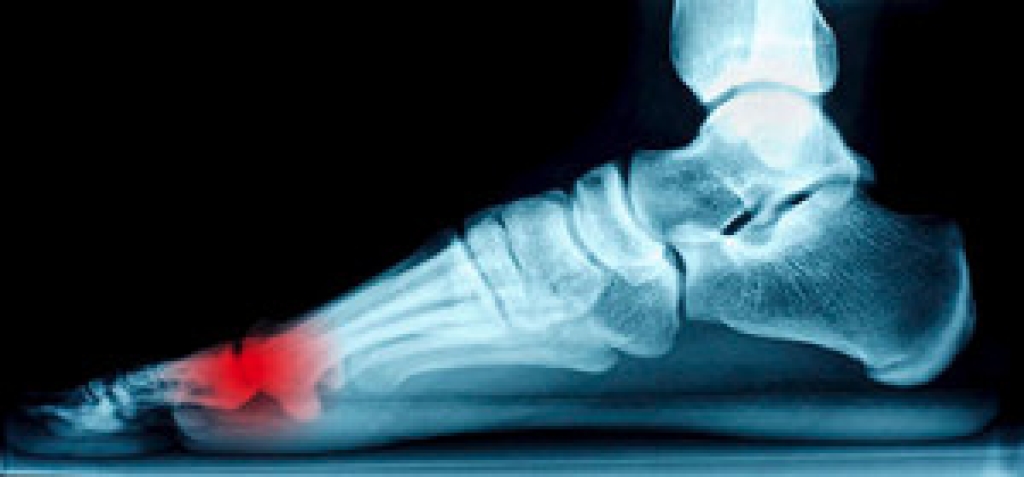

Sesamoid bones are unique in that they are not connected to other bones (which is normally the case with bones). Sesamoids are either embedded in muscles or connected to tendons. The kneecap (patella bone) is the largest sesamoid bone in the body. There are two little sesamoids in the foot which help the big toe move, enable the foot to push off, and serve as shock absorbers for the ball of the foot. When these sesamoids become fractured, irritated or inflamed due to repetitive pressure, overuse, or other contributing factors, it is known as sesamoiditis. Sesamoiditis can be quite painful, making it very difficult to walk. If sesamoiditis is not treated properly and promptly, other areas of the foot may become inflamed or even injured. If you are experiencing pain under the big toe and are having difficulty bending and straightening it, consult a podiatrist to see if you have sesamoiditis and receive proper care if you do.

Sesamoiditis

Sesamoiditis is a condition of the foot that affects the ball of the foot. It is more common in younger people than it is in older people. It can also occur with people who have begun a new exercise program, since their bodies are adjusting to the new physical regimen. Pain may also be caused by the inflammation of tendons surrounding the bones. It is important to seek treatment in its early stages because if you ignore the pain, this condition can lead to more serious problems such as severe irritation and bone fractures.

Causes of Sesamoiditis

• Sudden increase in activity

• Increase in physically strenuous movement without a proper warm up or build up

• Foot structure: those who have smaller, bonier feet or those with a high arch may be more susceptible

Treatment for sesamoiditis is non-invasive and simple. Doctors may recommend a strict rest period where the patient forgoes most physical activity. This will help give the patient time to heal their feet through limited activity. For serious cases, it is best to speak with your doctor to determine a treatment option that will help your specific needs.